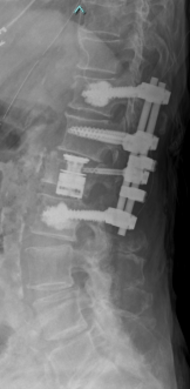

第2, 第3, 第4腰椎に前方への変性すべりを認めます。痛みのため背中を反って立てないことが分かります。MRIではいずれの椎間でも強い脊柱管狭窄が発生し、神経が圧迫されているのが分かります。

【術後】

スクリューとロッド、人工骨を使用した手術により腰椎の階段状変性すべりが整復され、痛みが改善したため腰を反って立つことが出来ています。第2腰椎の前方すべりは軽微であったため、金属は使わず除圧術のみに留めています。